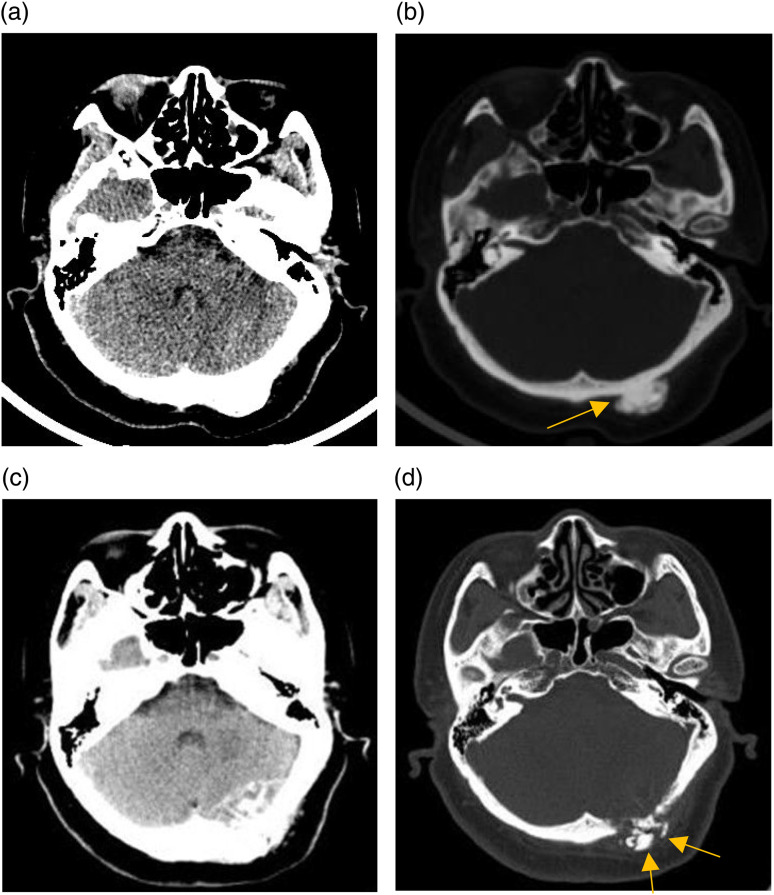

Osteosarcomas predominantly manifest in the long bones of the extremities, with rare occurrences in the skull. A case involving of a 53-year-old female who presented to the authors' hospital for examination due to dizziness was incidentally found to have an occipital bone mass, which was initially diagnosed as a benign tumor and did not receive sufficient attention. Two years later, owing to tumor enlargement, the patient underwent further evaluation at the same institution, which revealed evidence of occipital bone destruction. Pathological analysis confirmed the diagnosis of osteosarcoma. The patient underwent surgical resection followed by radiotherapy. Despite its infrequency and uncharacteristic initial presentation, skull osteosarcomas should not be overlooked.